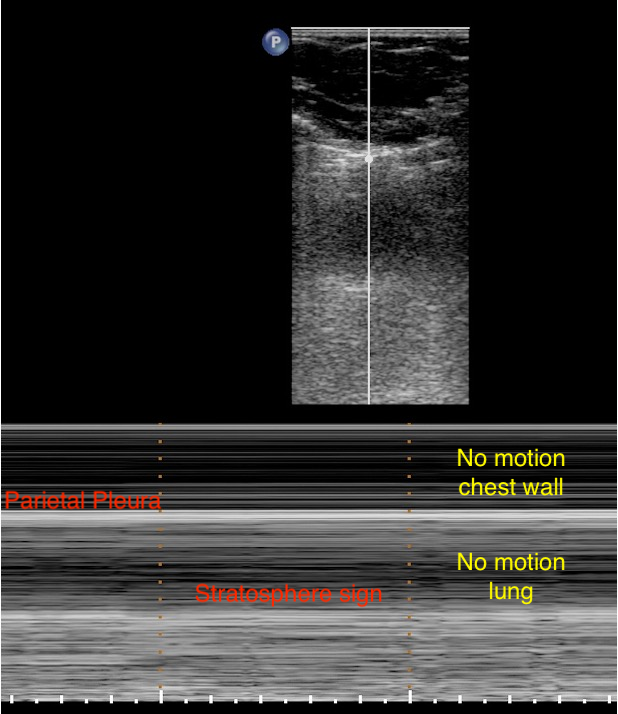

Artifacts

Pneumothorax